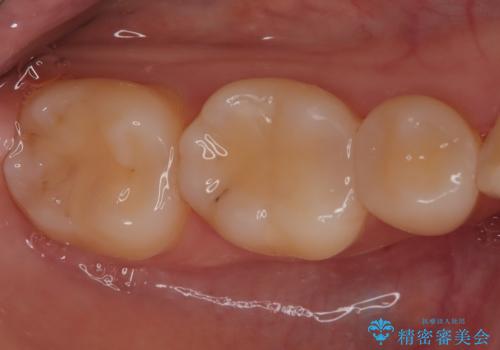

- 「銀歯を白しくしたい」を主訴に来院された患者さんです。

銀歯を外し、虫歯を除去した後にハイブリッドインレーで治療を行いました。

ハイブリッドインレーはセラミックと合成樹脂が混ざったものです。従って経年劣化や色の変化はあるものの、保険適応の被せ物に比べ、セラミックの含有率が高く、型取りの材料もシリコン材料を使用出来るので適合も優れています。